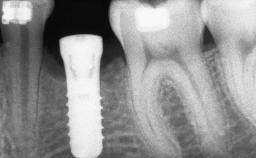

A 47-year-old woman who had suffered from aggressive periodontitis requiring a number of periodontal interventions over more than 10 years was referred by her general dental practitioner and periodontologist for bone augmentation and implant therapy. Her failing dentition had already been scheduled for extraction. The patient expressed a desire for implant-supported fixed restorations and esthetic improvement of her lower face. She had agreed to consult with a maxillofacial surgeon after the referring dentist had suggested bone augmentation. An initial examination by the maxillofacial surgeon revealed mobility of all residual teeth in a patient who was very unhappy with the function of her removable partial dentures. Due to periodontally migrated flaring teeth and loss of occlusal support, the vertical dimension of occlusion was dramatically reduced. The patient was displeased with her lower face because of deepened nasolabial, commissural, and supramental folds.

# of Implants 14

Bone Augmentation Horizontal|Sinus Floor Elevation|Staged|Vertical

Bone Volume Deficient vertically or deficient vertically AND horizontally